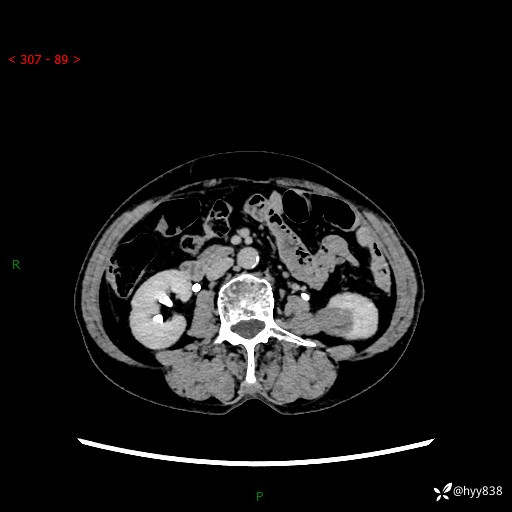

72岁/女,检查发现左肾占位1天。为了满足诊断,常规四期后,又加了延迟期-结果公布~

【患者信息】:72岁/女

【主诉】:检查发现左肾占位1天

【现病史及既往史】:患者于1天前检查发现左肾占位,无畏寒发热,无咳嗽咳痰,无腰腹部疼痛不适,无肉眼血尿、无尿频尿急症状,起病来,患者未行特殊治疗,为求进一步诊治,门诊以"左肾占位"收治入院。 发病来患者精神、饮食、睡眠良好,小便如上,大便正常,体重无明显变化。

【检查】:肾脏CT平扫+增强